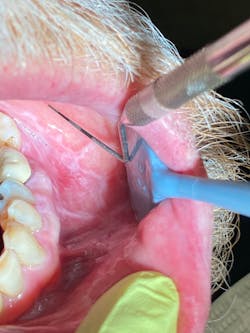

The OS had a lengthy discussion with the patient and subsequently recommended a biopsy to assure a definitive diagnosis. The patient declined. His reasons were personal, and according to the OS’s office, he was concerned about finances.

After seeing the OS, the patient stopped back by my office to discuss his concerns. I informed him that I had also talked to the OS about his case. The patient’s humble honesty about his reluctance to get a biopsy (aside from his financial situation) was because he didn’t want to put himself in a situation that could potentially compromise his ability to see to his wife’s needs. Simply put, she was his priority right now, and despite the simple nature of a biopsy, he didn’t want to consider it at this time.